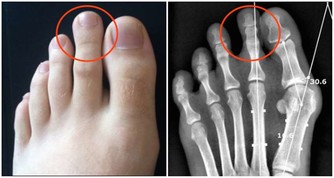

有發疹、劇烈頭痛、關節痛、痙攣症狀。